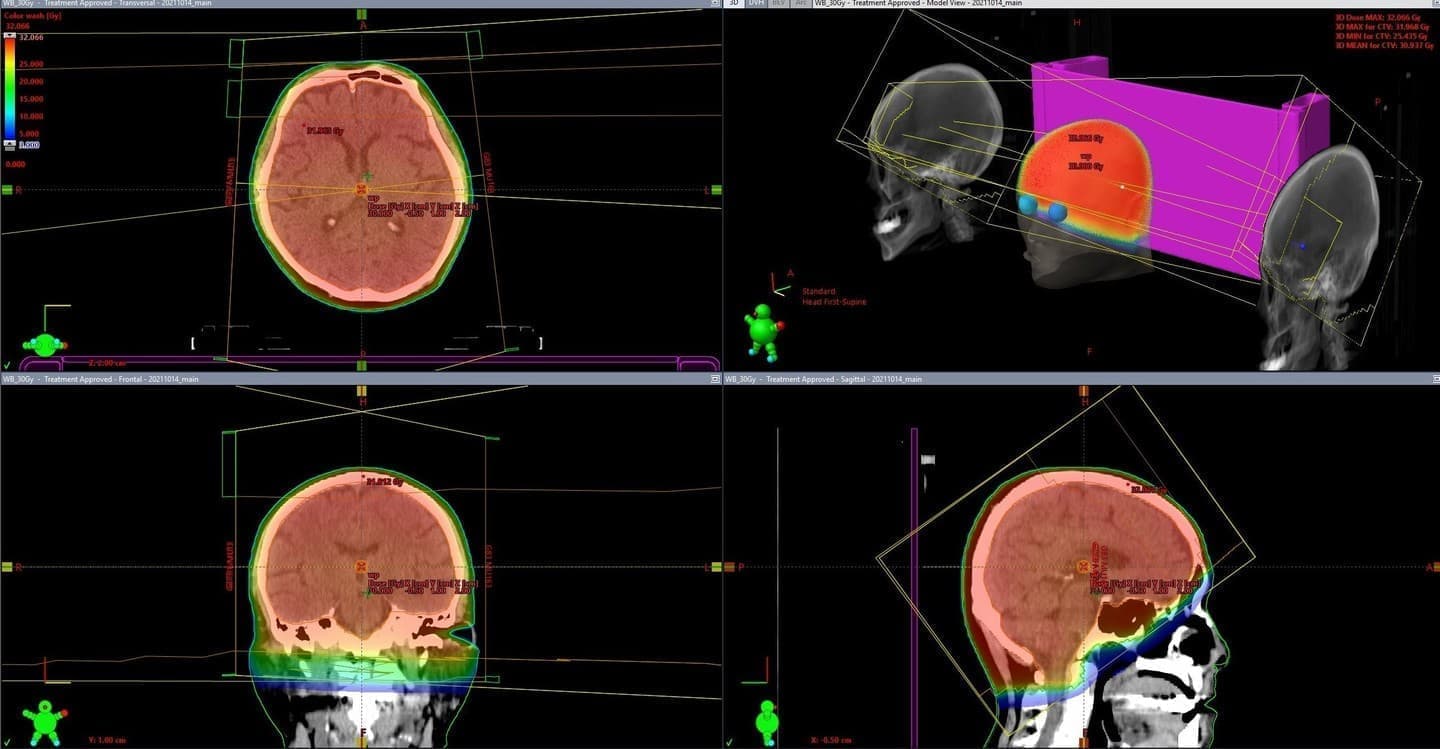

最新鋭の放射線治療装置を導入しており、強度変調放射線治療(IMRT)やピンポイントでがん組織を狙い撃ちする定位放射線治療(SRT)などを、位置照合を正確に行う画像誘導放射線治療(IGRT)により、がん組織に集中して放射線を照射することが出来ます。

健康組織への影響を最小限に抑えた、患者さんの身体に優しい治療をすることが可能です。

TrueBeam STx(Varian)

2.5mm幅のマルチリーフコリメータを搭載した最新鋭高精度放射線治療装置。

6MV, 10MV, 最大1400MU/min, 2400MU/minの高出力が可能な6MV-FFF(Flattning Filter Free)、10MV-FFFの4種類の高エネルギーX線、6, 9, 12MeVの3種類の電子線が使用可能。

ExacTrac system(BrainLab)併設による高精度な位置照合を実現しています。

がんなどの治療標的を取り巻く正常組織へ放射線が当たることを避け、VMAT(強度変調回転照射)、SRS(定位放射線手術)、SRT(定位放射線治療)、SBRT(体幹部定位放射線治療)を行っています。